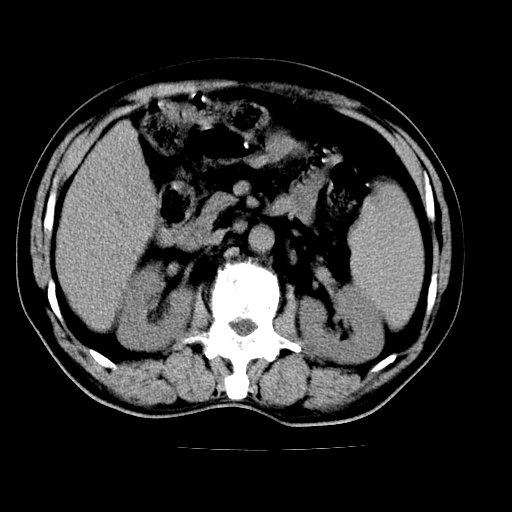

男,66岁,上腹部不适、黄染一周。彩超示:肝左叶占位,肝内胆管扩张,胆总管扩张,胆总管占位?

肝左叶不规则软组织肿块影,边缘不规整邻近肝实质受累分界不清;肝内胆管(左叶)明显扩张成“软藤状”,诊断:肝左叶胆管细胞癌。

肝左叶占位性病变,并胆管扩张,符合胆管细胞癌ct表现,门脉左支受累,左肾囊肿。窗宽太窄了,其他的看不清

左叶胆管细胞癌累及胆总管,门脉左支受侵,慢性胆囊炎胆结石,左肾小囊肿

肝左叶不规则软组织肿块影,边缘不规整邻近肝实质受累分界不清;肝内胆管(左叶)明显扩张成“软藤状”,诊断:肝左叶胆管细胞癌。胆囊钙乳症。